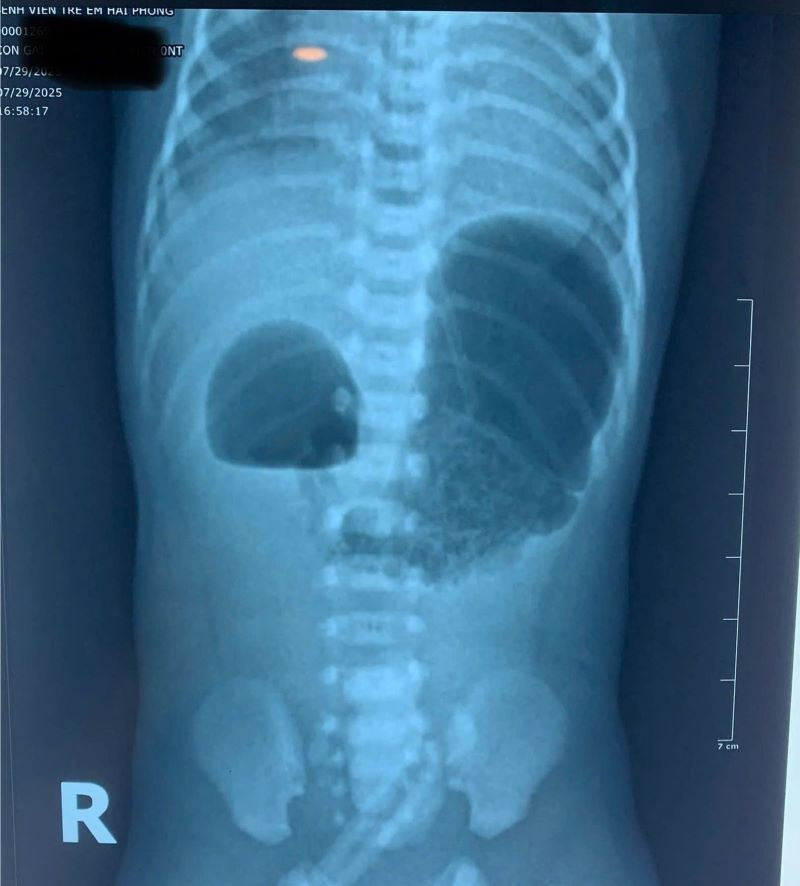

Hình ảnh tắc tá tràng bẩm sinh trên phim chụp - Ảnh BVCC

Khi nhập viện, bé ở trong tình trạng mất nước, thóp lõm, rối loạn điện giải và thiếu máu. Các bác sĩ đã nhanh chóng tiến hành hồi sức tích cực, nuôi dưỡng tĩnh mạch và bù điện giải, quá trình khám và làm các xét nghiệm chẩn đoán hình ảnh phát hiện trẻ bị tắc tá tràng bẩm sinh.